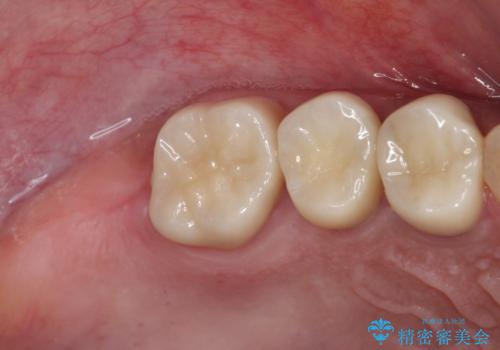

- 奥歯を治療しようと他院で開始したものの、放置してしまったとのことで来院された患者様です。

外れてしまった銀歯や穴の空いた仮歯などあり、適合の悪い被せものと合わせて、セラミッククラウンやセラミックインレーにて治療と行うこととしました。

億劫に感じて治療を先延ばししていたそうですが、始めてみるとスムーズに治療が終わり、早く始めておけば良かったと仰っていました。